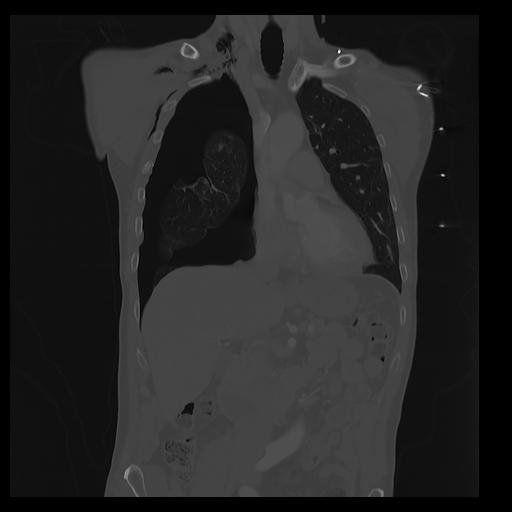

32 PULMON,CE,Coronal,3.000,PULMON,Coronal,